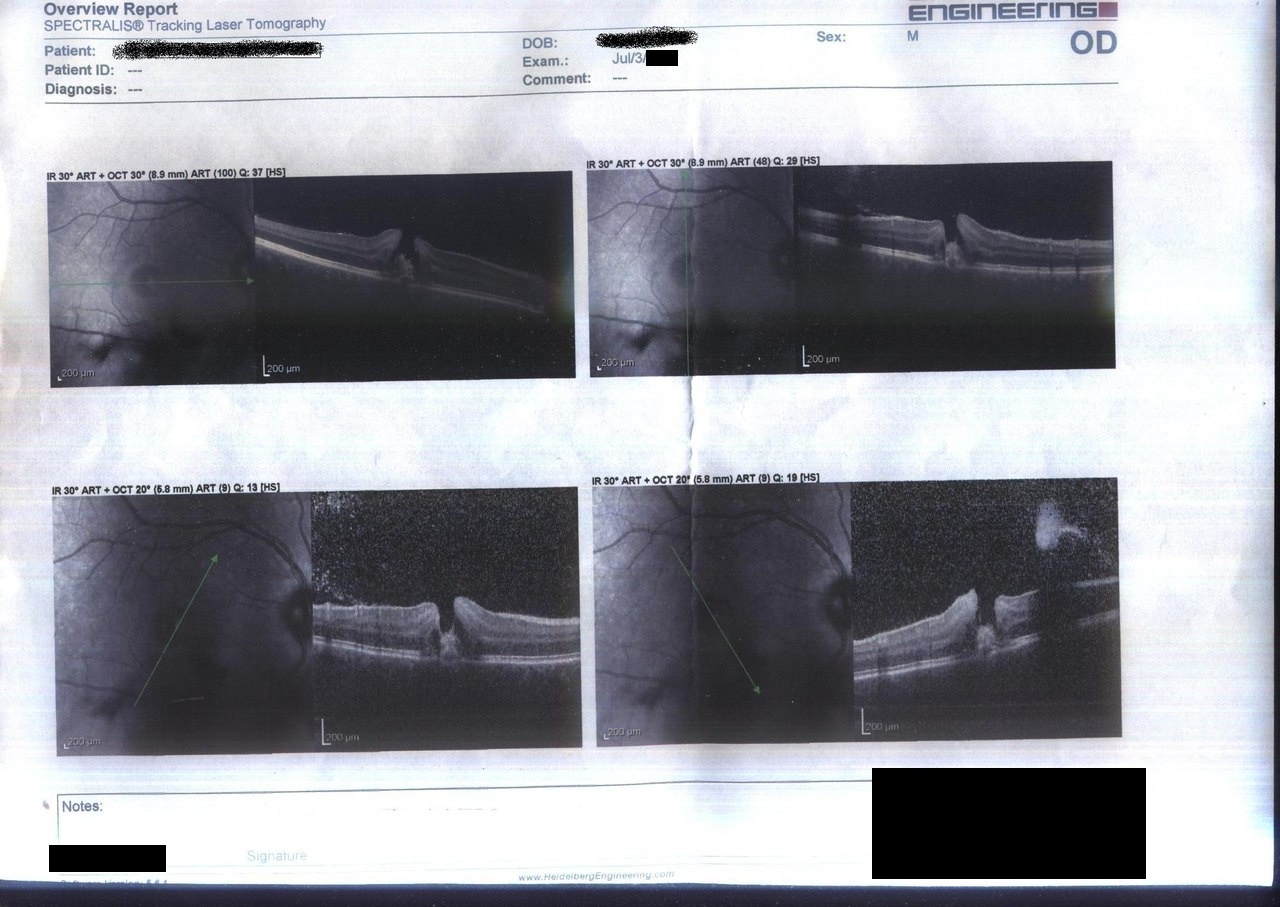

Теперь посмотрим, так сказать, наглядно, как выглядит травма глаза лазерным излучением. Я уже упоминал, что в поисках новых лазеров и их компонентов я посещаю различные организации. И однажды я посетил лазерное отделение местного центра лечения глазных болезней. В ходе общения со специалистами, я поинтересовался, попадались ли в их практике травмы, вызванные лазерным излучением. Ответ меня удивил. Дело в том, что за более чем 20летнюю практику работы, непосредственно лазерных травм было всего несколько штук. На мой вопрос, типа как так, если сейчас у каждого ребенка есть лазерная указка от 50 до 2000 мВт, лишь ответили, что людей с ожогами от указок не поступало. Зато было много людей именно с солнечными, нелазерными, ожогами сетчатки. Мне показали документы по наиболее примечательной лазерной травме – сильному повреждению центральной ямки сетчатки, вызванному зеркально отраженным импульсом из лазерного дальномера, построенном на импульсном неодимовом лазере (Nd:YAG) работавшем в режиме модуляции добротности. Энергия импульса составляла по разным оценкам от 20 до 100 мДж, при длительности импульса порядка 20 нс. Именно из-за модуляции добротности повреждение вышло столь тяжелым – так как в точке фокуса излучения был оптический пробой, вызвавшим гидравлический удар, который в свою очередь привел к центральному разрыву сетчатки и отеку последней совместно с гемофтальмом (кровоизлиянием в стекловидное тело). Мне разрешили просканировать документы на условиях их полной анонимизации. С помощью оптической когерентной томографии можно рассмотреть сетчатку в разрезе, в различных плоскостях. Так выглядел разрез на момент обращения за медицинской помощью. Видна четкая «пробоина» с «отогнутыми наружу» краями (на самом деле это отек).

Более крупным планом:

И в разных плоскостях:

Из текста предоставленных мне документов стало известно, что курс лечения длился 10 дней, по ходу которого решался вопрос об операции, в случае отслоения сетчатки. В качестве оперативного вмешательства по устранению возможной отслойки и закрытия разрыва предлагалась пневморетинопексия (ПРП). Консервативное лечение было направлено на рассасывание отека и предотвращение воспалительного процесса. По ходу наблюдения делалось также несколько фотографий глазного дна, а по окончанию курса было решено, что операция не понадобится, так как разрыв самостоятельно закрылся и зарос рубцовой тканью.

В кучке этих же документов лежала ещё одна распечатка оптической когерентной томографии после окончания лечения.

Как можно видеть, канал пробоя исчез, а края того места, которое было центральной ямкой приняли более сглаженные формы. На момент травмы острота зрения по табл. Сивцева составляла 0%, после окончания лечения было достигнуто улучшение до 30%. На мой вопрос, как это воспринимается субъективно, мне показали ещё одну картинку, на которой наглядно показано, что такое «центральная скотома». Это слепое пятно, из которого просто выпадает часть изображения. же способен «закрасить» его под цвет окружающего фона, но никаких деталей изображения видно не будет, так как нечем их видеть – светочувствительные клетки в этом месте уничтожены. Для данной статьи картинка взята из гугла. Также мне объяснили, что при наличии второго здорового глаза это слепое пятно не влияет на качество жизни.